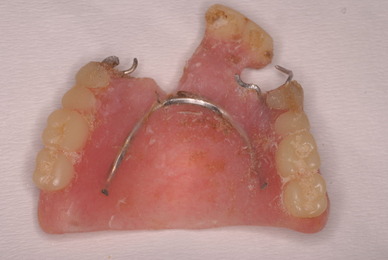

下顎です。